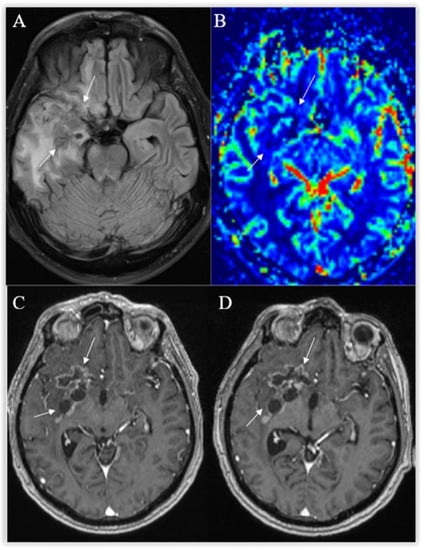

3.3. Perfusion-Based Imaging

3.3.1. Dynamic Susceptibility Contrast

3.3.2. Dynamic Contrast Enhancement

3.6. Posttreatment Imaging

3.6.1. True Progression

3.6.2. Pseudoprogression

3.6.4. Radiation Necrosis